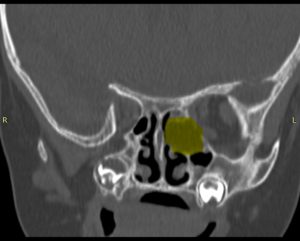

CT și RMN cranio‑faciale au evidențiat (Fig. 1):

- Formațiune tumorală etmoido‑orbitală stângă, cu extensie spre vârful orbitei;

- Distrucția prin compresie a peretelui medial orbital stâng, fără efracția periorbitei.

- Protruzia intraorbitară a formațiunii. Nu se pune in evidență extensie intracraniană

Figura 1: Secțiuni CT preoperatorii in plan axial si coronal, evidențiind tumora etmoido‑orbitală stângă.